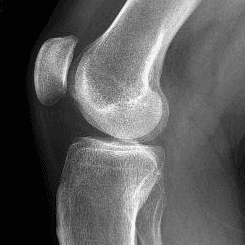

posterior hornda grade-3 yırtık izlenmektedir. mrhblar.kolayy gelsin.halı sahada dizimle ilgili ciddi bir sorun yaşadım ve mr çektirdim sonucum aşağıdadır.3. Derece yırttık bir sorun farkındayım ama bu yırtığın olduğu yer sizce çok mu ciddi ameliyatsız bir şekilde güçlendirme ile düzelme ihtimali var mı Os fabella izlenmektedir. Retropateller alanda hafif sıvı artışı izlenmektedir. Retropatellar ve femoratibial kartilaj yapıları normaldir. PCL, MCL, LCL, ve patellar tendon kalibrasyonu ve sinyal intensitesi normaldir. ACL devamlılığı izlenmekte, internal sinyal instensitesi artmıştır(Parsiyel rüptür). Lateral menüsküs anterior horn normal, posterior horn normaldir. Medial menüsküs anterior horn normal,posterior hornda grade-3 yırtık izlenmektedir.